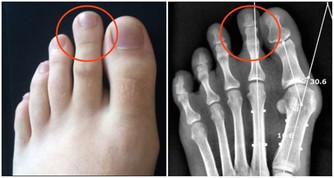

*****4. 糞便很細,排便不爽*****

一旦持續一段時間排出的均為柔軟的細便,並且總有排不盡的感覺,要特別注意,需要接受內鏡檢查。